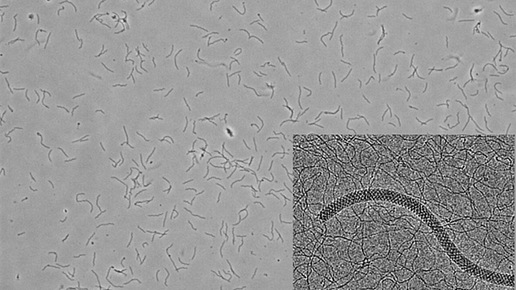

Полученные результаты могут оказать влияние на лечение инфекций в будущем, поскольку растет обеспокоенность по поводу возникновения антибиотикорезистентных штаммов. Исследование было опубликовано в журнале ACS Chemical Biology. «Многие виды бактерий должны иметь возможность двигаться, чтобы инфицировать организм хозяина», - говорит соавтор статьи Брайан Крейн. «Подвижность может быть важна для перемещения между хозяевами - например, от клещей к человеку, - а также для распространения внутри хозяина, колонизации наиболее благоприятных тканей и уклонения от иммунной системы»...